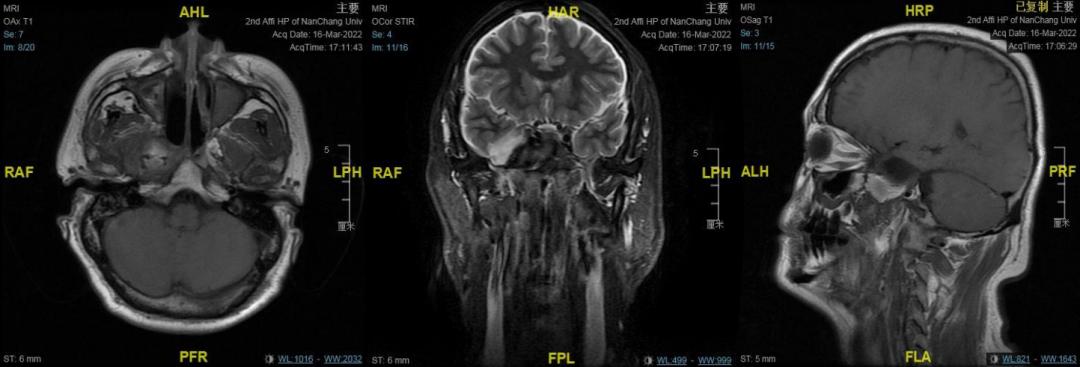

颅脑MRI平扫+增强

右侧中颅窝鞍旁见一大小约34mm✕40mm✕47mm肿块,信号混杂,T1、T2均呈等低高混杂信号,DWI呈不均匀混杂信号,边缘包膜呈稍长T1短T2信号,肿块边界清;肿块无强化,边缘包膜呈明显强化